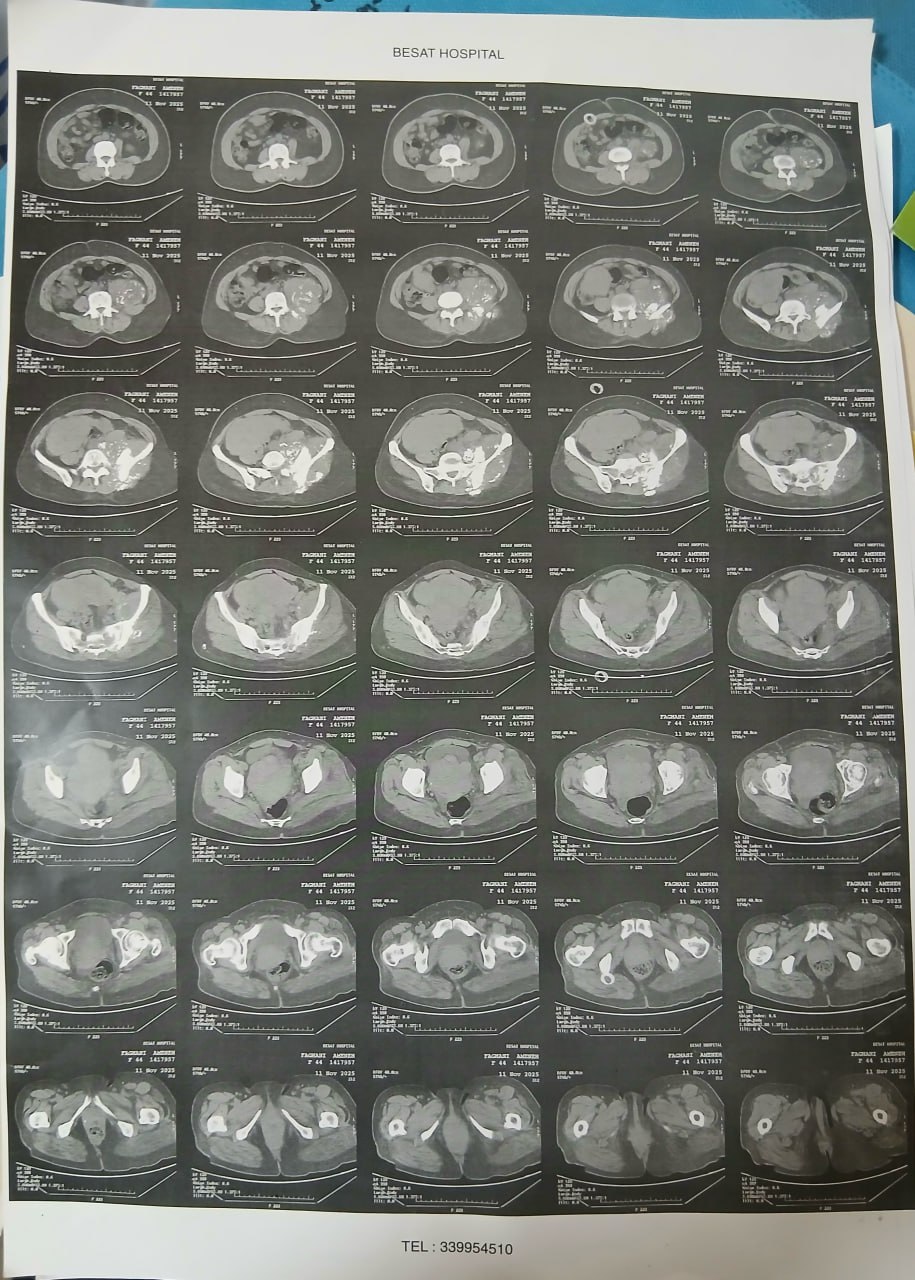

در بررسیهای تصویربرداری (MRI)،در تاریخ 24.7 ، تودهای با تشخیص کندروسارکوما همراه با DVT گزارش شده است. بیمار سابقه درد لگن داشته که شدت آن در حال حاضر نسبت به گذشته کاهش یافته است. به گفته بیمار، حجم توده در ابتدا در حدود اندازه یک تخممرغ بوده که در حال حاضر کاهش یافته است. همچنین تورم اندام تحتانی در حال حاضر نسبت به قبل کمتر شده است.

مراجعه کرده است. پس از بررسی های انجام شده در MRI انجام شده توده با درگیری مفصل ساکروایلیاک چپ و DVT؛ ابتدا تحت درمان DVT قرار گرفته است و سپس جهت پیگیری تومور رویت شده تحت بیوپسی قرار گرفته است و با تشخیص کندروسارکوما به این مرکز مراجعه کرده است و تحت کموتراپی و رادیوتراپی قرار گرفته و سایز تومور کاهش یافته است.

(تصویر مربوط به این مراجعه نیست) Other: